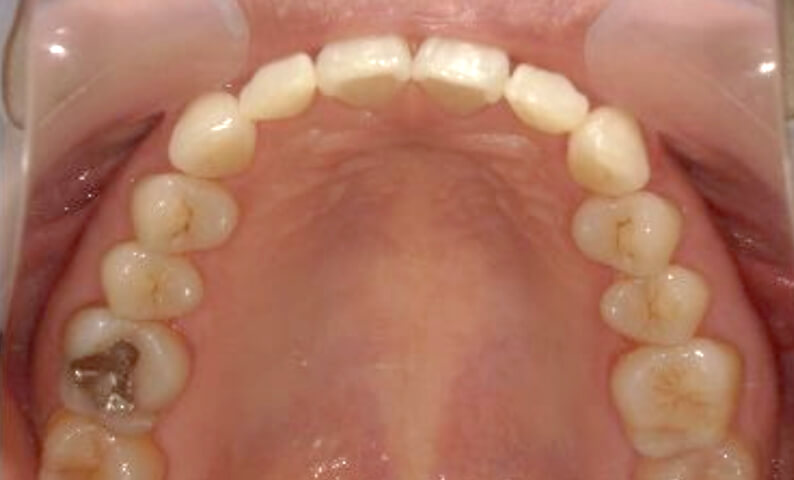

症例_002 上顎だけの部分矯正

治療期間:7ヶ月金額:30万円+税女性前歯のガタガタ上の前歯だけ

| Before | After |

|---|---|

|